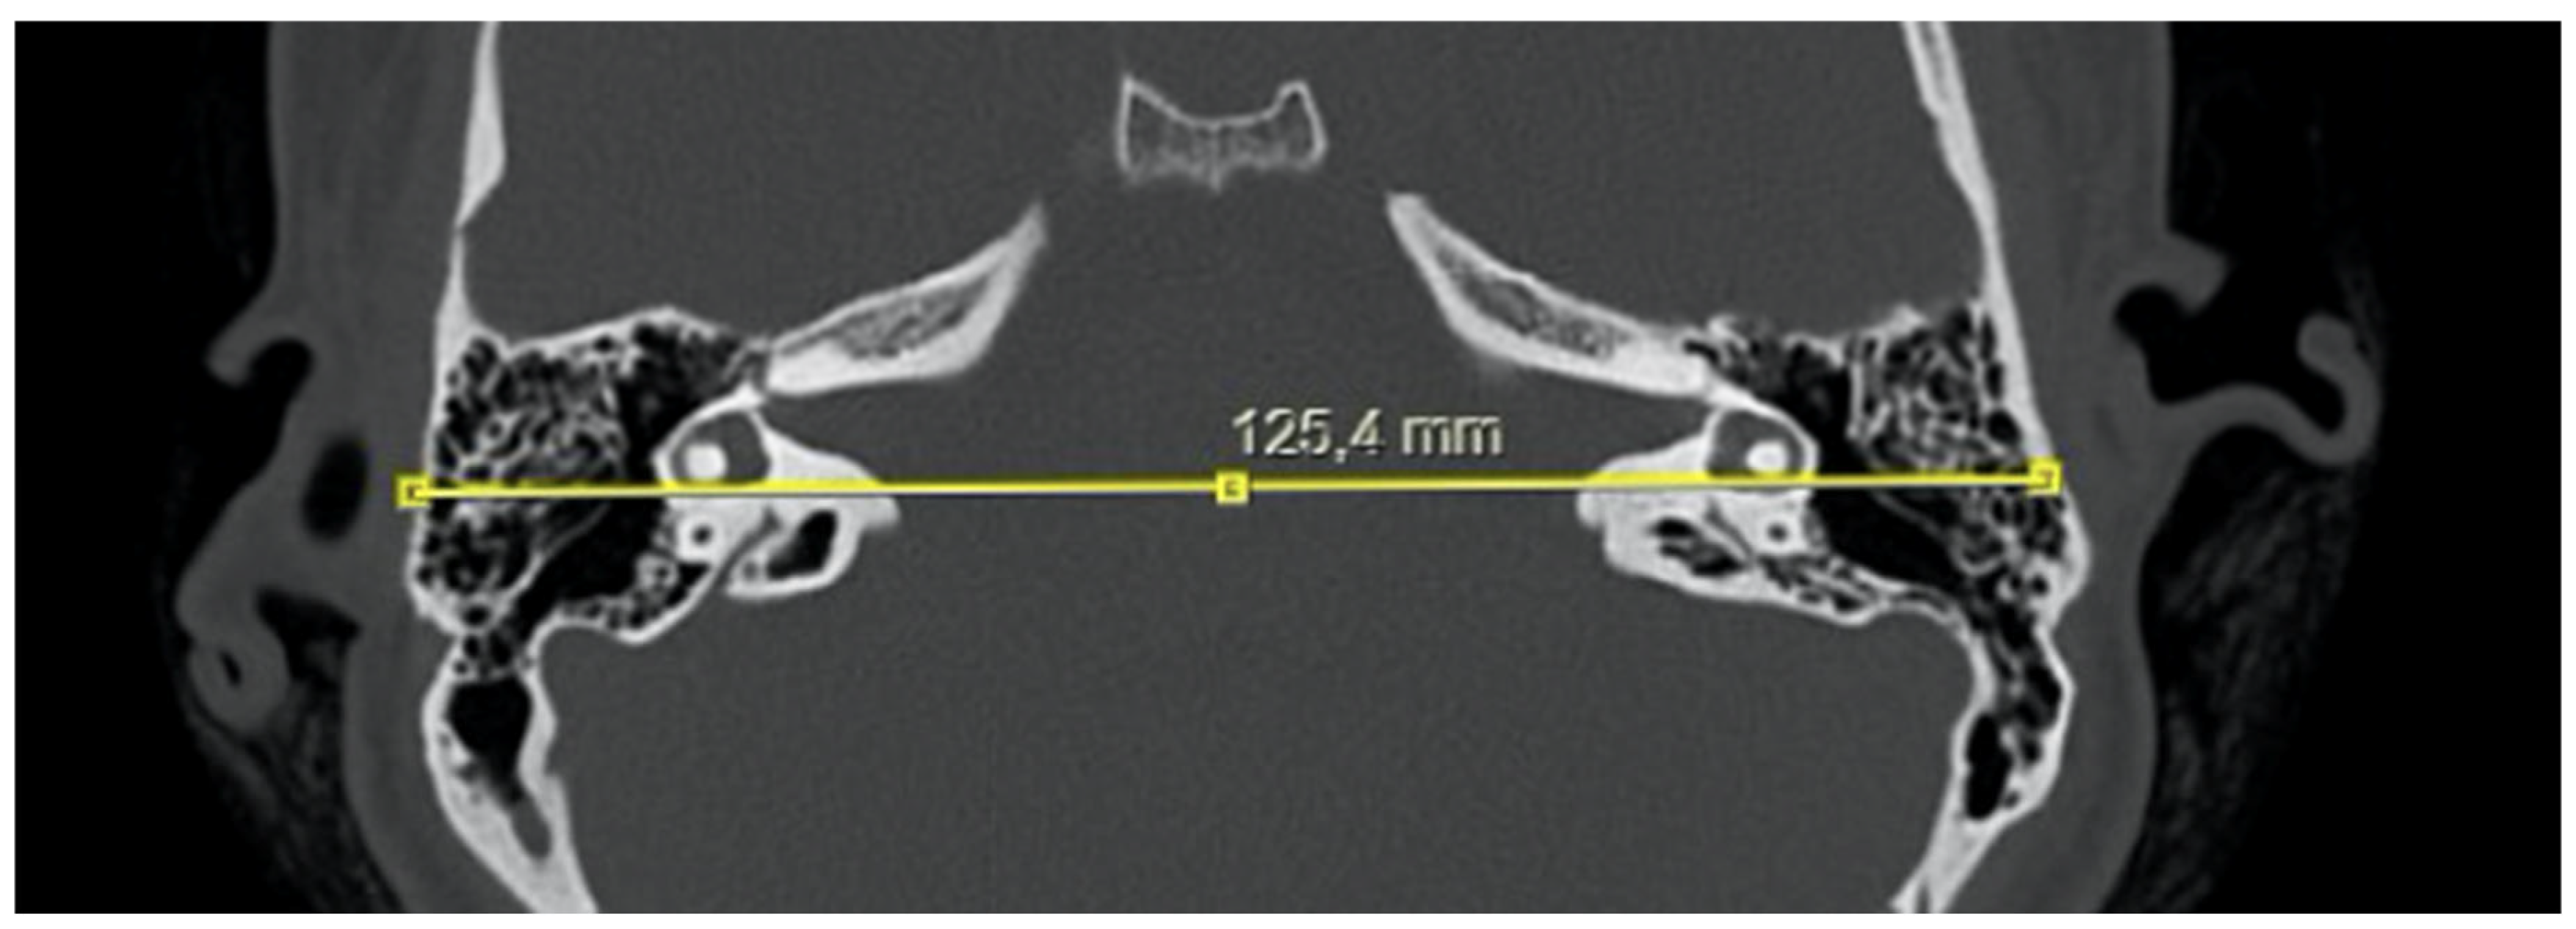

- Bitemporal distance: the tangential line passing posterior to the lateral semicircular canals, measuring the distance between the cortices of both temporal bones (Figure 1);